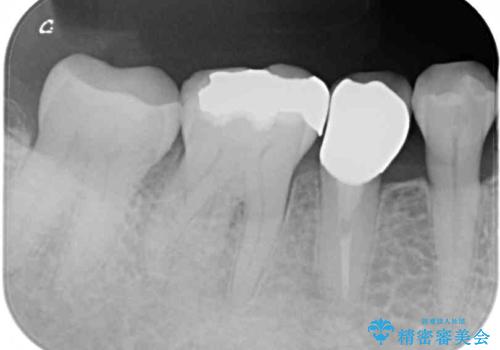

虫歯を全て除去したうえで新しい土台を築製し、セラミッククラウンにより補綴治療を行うこととしました。

虫歯が歯根深くまで及んでいる場合には歯を部分矯正で引っ張り出したり、歯周外科処置が必要となったりしますが、メインテナンスでレントゲン写真を定期的に撮っていたため、幸いにも矯正や外科処置が必要となる前に補綴治療を行うことができました。